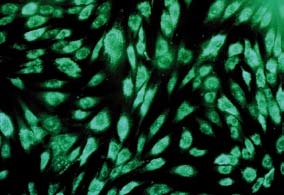

A o co vlastně jde? Pacientovi se odebere malá část chrupavky (2 x 3 mm), ze které se v superčistých prostorách laboratoří NTC a. s. vyizolují buňky pacienta zodpovědné za tvorbu chrupavky (chondrocyty). Buňky jsou následně tři až čtyři týdny kultivovány v laboratoři NTC a. s., než je dosaženo jejich potřebného počtu. Pak jsou smíchány s tkáňovým lepidlem a je vytvarován požadovaný tvar nové chrupavky. Nová chrupavka je přepravena do nemocnice, kde ji lékař pomocí tkáňového lepidla implantuje pacientovi do místa defektu. „Defekt chrupavky se vyplní vlastními buňkami pacienta, což je zásadní výhodou oproti jiným metodám, které jsou technicky náročné a způsobují vysoké zatížení pacienta, jako například implantace autologních osteochondrálních štěpů (mozaiková plastika). Naopak využití vlastních buněk je nejlevnější metodou léčby a zároveň se při těchto postupech zvyšuje kvalita života. Zatím dosahujeme špičkových klinických výsledků a za celé období aplikace nebyly hlášeny ani zjištěny žádné nežádoucí účinky, pooperační komplikace nebo selhání implantátu," dodává MUDr. Kubešová.

Chondrograft patří do tzv. kategorie léčivých přípravků Moderní terapie (z angl. názvu Advanced Therapy Medicinal Products). Tyto léčivé přípravky posouvají hranice biologické a cílené léčby. Lze je klasifikovat jako biologické implantáty, které dle svého charakteru zvyšují kvalitu života lidí a pomáhají lékařům vrátit nemocné do aktivního plnohodnotného života. U většiny lékařských zákroků, kde je možné léčivé přípravky Moderní terapie použít, dochází k plné biologické léčbě prostřednictvím vlastního buněčného materiálu pacienta, a tak navíc dochází ke striktně personalizovanému přístupu k léčbě.

Jakmile je chrupavková tkáň odebrána, je převezena do laboratoří NTC, kde se následně zpracovává v tzv. „superčistých prostorách". Z tkáně jsou získány chrupavkové buňky, které jsou dále množeny až do požadovaného počtu. Doba, za kterou jsou buňky namnoženy, je individuální, dle růstu buněk (i chrupavkové buňky rostou každé jinak rychle). Pro nárůst dostatečného počtu buněk je třeba doba přibližně 3-4 týdnů. Poté, co je dosaženo vhodného počtu buněk (záleží na velikosti připravovaného chondrograftu), jsou buňky smíchány s takzvaným tkáňovým lepidlem, aby vznikla nová chrupavka, která vyplní chybějící nebo poškozenou část chrupavky. Velikost připravované chrupavky je dána velikostí poškozené chrupavky, kterou lékař zadá již na počátku kultivace buněk.